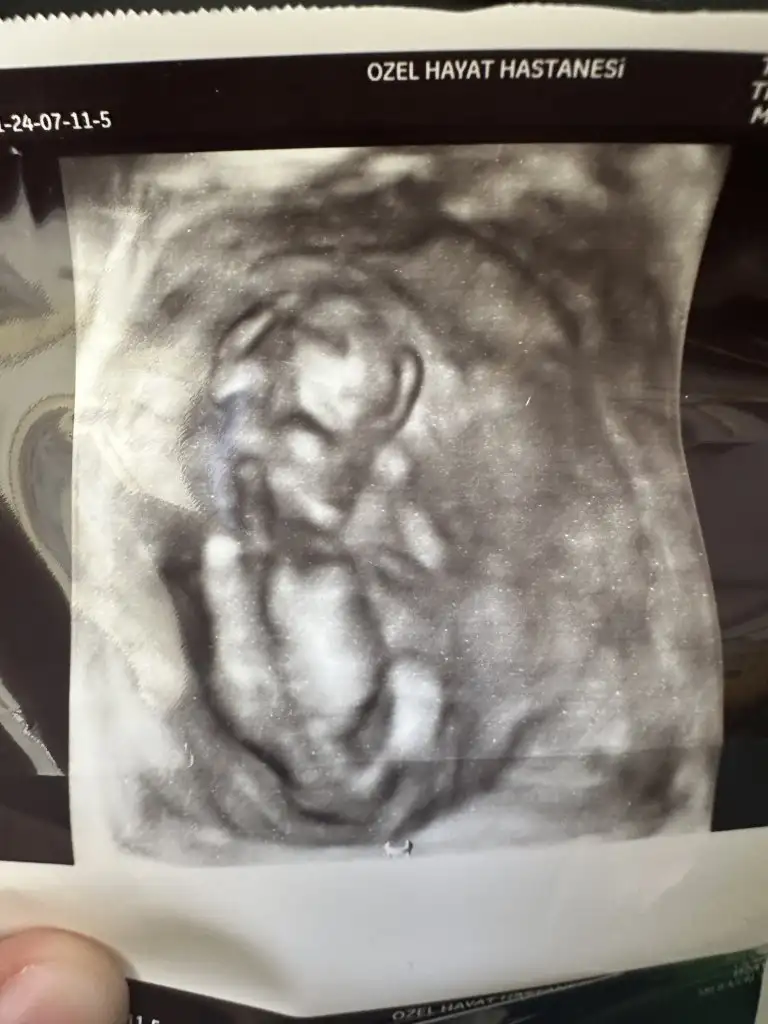

13+5 de doktora gittim cinsiyet görünmedi kız gibi dedi çıktını var ama bu haftalarda kızda da erkek de oluyor çıkıntı dedi doktorum yurt dışına çıktı 14+5 de ağrılarım oldu devlete gittim cihazım aşırı kötü kızda diyemem erkek de çıkıntı var ama kızda olabilir dedi ama tahminim erkek dedi ama bizim gördüğümüz bacak arası boştu birde siz bakarmınızEki Görüntüle 3296428

Kız bebek bacak arası boş 😍